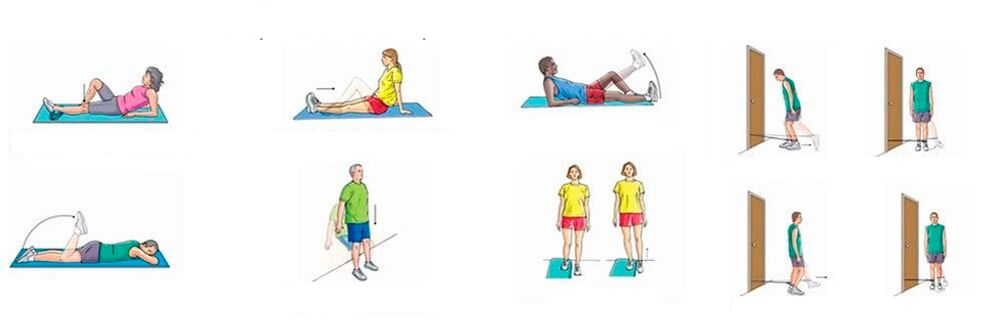

Belauneko artikulazioetako min kronikorako, hantura nabarmenik ez dagoenean, muskulu-ligamentous sistema indartzen duten ariketa fisikoak egin ditzakezu, odol-zirkulazioa eta metabolismoa hobetzeko. Entrenamendu sistematikoak mina pixkanaka gutxitzea dakar, hankak nahiko kurruskariak izan arren.

Belauneko minerako gutxi gorabeherako ariketa multzoa:

- Belauna finkoa. Etzan zaitez bizkarrean, okertu hanka bat belaunean, altxa ezazu eta eutsi egoera honetan minutu batez; bigarren hanka geldirik dago momentu honetan; zuzendu eta jaitsi hanka oso poliki, atseden hartu 10 segundoz eta errepikatu ariketa beste hankarekin; errepikatu 10 aldiz;

- Hanka bikoitza tolestuta belaunak aurpegitik gertu. Etzan zaitez bizkarrean, tolestu hankak aldaketan eta belaunetan, konpondu azken hau aurpegiaren ondoan eta eutsi horrela minutu batez. Ondoren, poliki-poliki zuzendu eta jaitsi hankak, atseden hartu 10 segundoz eta errepikatu; egin 5-6 hurbilketa, karga pixkanaka handituz.

Belauneko artikulazioko min akutua izanez gero, larruazalaren hantura eta gorritasuna, egoera orokorra urratzea, sukarra, ezin duzu hanka mugitu, atseden hartu behar da. Eta hantura jaisten hasi ondoren, lehenik eta behin ariketa pasiboetara (laguntzaile batek egindakoak) eta gero ariketa aktiboetara (gaixoak berak egindakoak) mugi zaitezke.